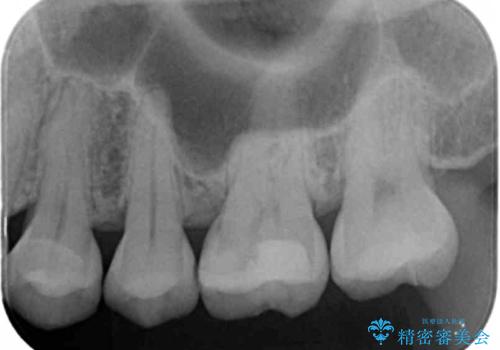

- 検査の結果、歯と歯の間に虫歯が見つかった患者様です。

白く目立たないものでの治療をご希望されたため、セラミックインレーでの治療となりました。

- 左上5 セラミックインレー 77,000円費用は治療当時の料金となります

歯と歯の間は虫歯の好発部位です。

適合の良いセラミックインレーで修復することで見た目の綺麗さを保ったまま治療することができます。